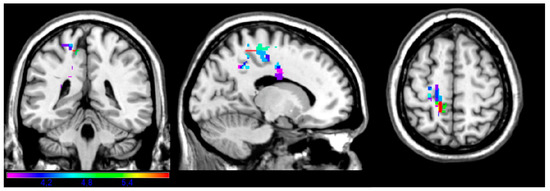

Post-stroke language recovery remains one of the main unresolved topics in the field of aphasia. In recent years, there have been efforts to identify specific factors that could potentially lead to improved language recovery. However, the exact relationship between the recovery of particular language functions and possible predictors, such as demographic or lesion variables, is yet to be fully understood. In the present study, we attempted to investigate such relationships in 42 patients with aphasia after left hemisphere stroke, focusing on three language domains: auditory comprehension, naming and speech fluency. Structural imaging data were also obtained for the identification of the lesion sites. According to our findings, patients demonstrated an overall improvement in all three language domains, while no demographic factor significantly contributed to aphasia recovery. Interestingly, specific lesion loci seemed to have a differential effect on language performance, depending on the time of testing (i.e., acute/subacute vs. chronic phase). We argue that this variability concerning lesion–deficit associations reflects the dynamic nature of aphasia and further discuss possible explanations in the framework of neuroplastic changes during aphasia recovery. Full article

Show Figures

Figure 1